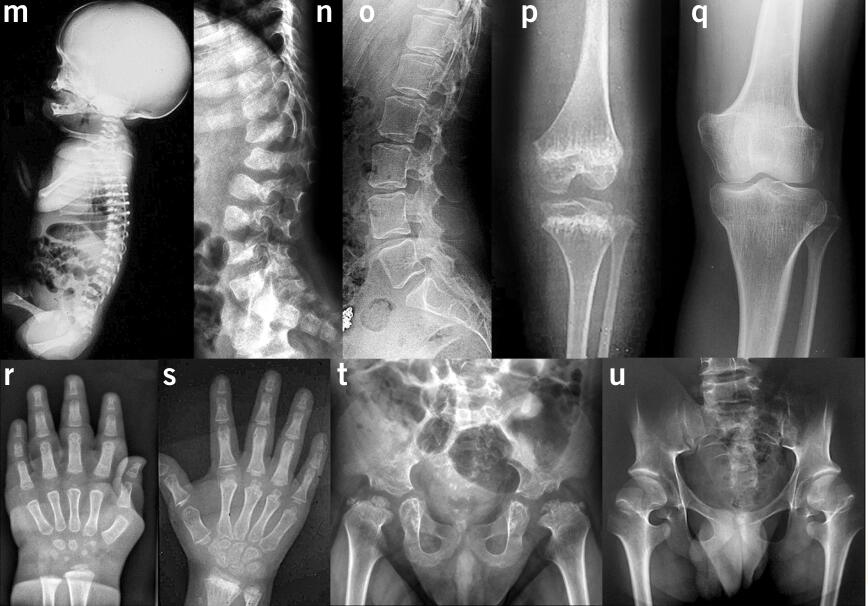

另一种遗传障碍性疾病,俗称骨骼发育不良疾病,虽然没有智力发育障碍如此常见,但对婴幼儿的影响仍十分巨大,此处介绍的就是一种表现出严重的智力发育障碍与骨骼发育不良两种缺陷的遗传性疾病。对六个家庭的九个患者进行研究后发现:这种疾病的主要临床特征包括产前脑积水、不成比例四肢短小、肌张力低下,早期发展里程碑如坐和行走的推迟等。随后,发育迟缓、认知障碍以及是否能独立生活等都是医学上的关注的重点。

首先,将来自6个家庭的十种不同变种进行分析,其次用细胞实验和底物确认,最后在斑马鱼胚胎上进行了实验,发现酶失活会导致斑马鱼上出现包括骨架结构发育异常在内的复杂表型。数据显示,这种疾病是由先天性新陈代谢缺陷引起的,影响唾液酸(NeuNA)的内源性合成。探究这种疾病的生物化学和分子特征可以进一步研究唾液酸在大脑和骨骼发育中的作用。

大脑是所有人体器官中含有总唾液酸最高的器官,唾液酸主要分布于糖蛋白和糖脂,如神经节苷脂在神经组织特别丰富,NANS在人脑中高度表达。在九个发病严重发育迟缓和骨骼发育不良的个体中检测NANS(编码N-乙酰神经氨酸,又称唾液酸)的等位基因突变后发现,都存在NANS表达减少的现象。